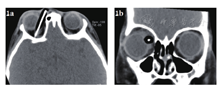

急诊入院者16例,均行眼眶CT检查,其中6例患者发现异物影(37.5%),发现异物影者主要为铅笔或筷子类异物(图1a、b),而竹子类异物较难发现,多表现为絮状密度影等感染征象、不能显示明显异物影(图1c、d);早期入院者7例,均行眼眶CT检查,其中4例发现异物影(57.1%),表现为条状或片状低密度影,周围伴软组织密度影(图2);中晚期入院者19例,4例在外院行了眼眶CT外余均在我院行眼眶CT检查,其中16例扫描表现为高密度条索状或片状异物影(84.2%),大部分能显出异物大致轮廓,周围多伴有软组织密度影(图3)。